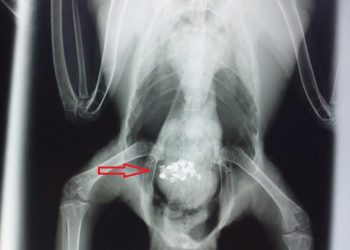

Read moreDetailsEvcil Kuşlarda gut hastalığı, insanlar ve sürüngenler ve kanatlılar arasında yaygın bir hastalıktır. Özellikle muhabbet kuşları, su kuşları ve kümes...